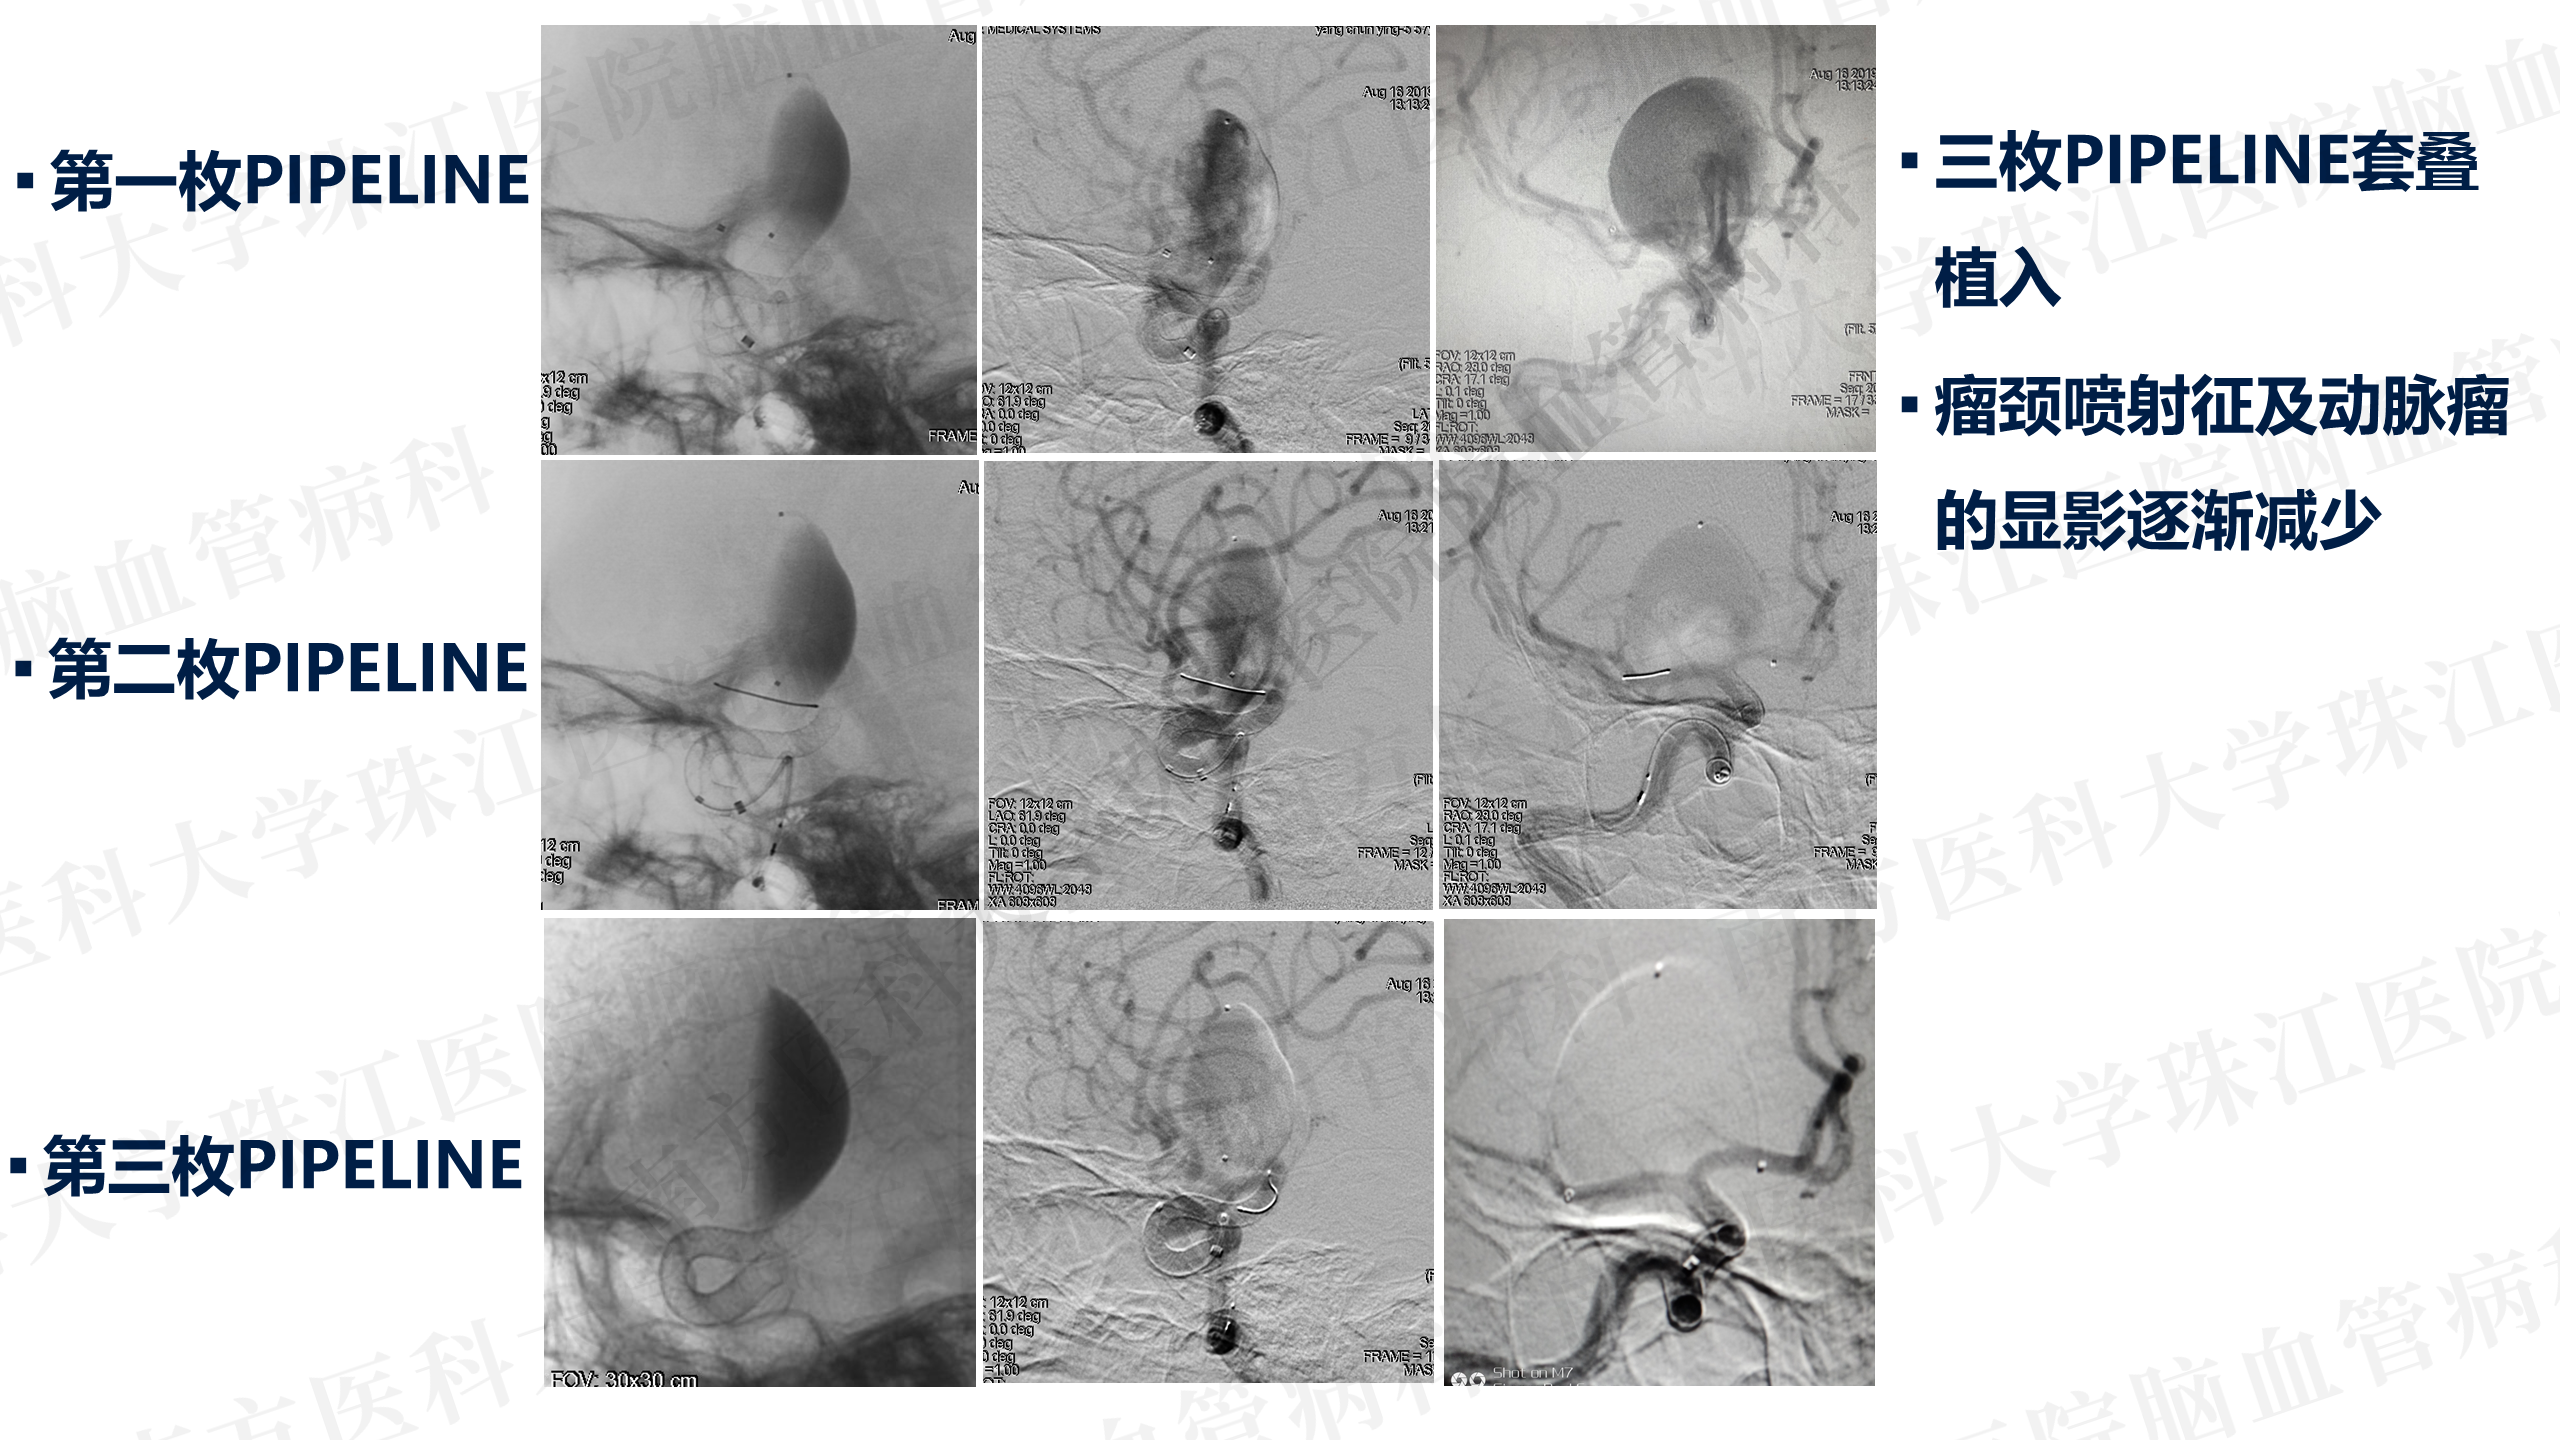

患者入院后造影发现“颈内动脉床突上段巨大动脉瘤,大小约2.7x3.5cm。决定行PIPELINES密网支架植入治疗。

晚上急诊造影

患者入院后造影发现“颈内动脉床突上段巨大动脉瘤,大小约2.7x3.5cm。决定行PIPELINES密网支架植入治疗。

晚上急诊造影